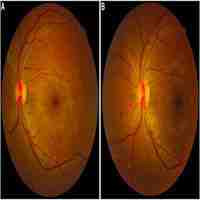

| Abstract | Background Diabetic retinopathy is the main cause of preventable blindness in the economically active population in western countries. Diabetic retinopathy screening is effective in preventing blindness and can be performed through various diagnostic methods. Our objective is to compare binocular indirect ophthalmoscopy (BIO) to telemedicine protocols of digital retinography for diabetic retinopathy screening in a large and heterogenous type 1 diabetes population in a developing country. Methods Data from 1266 Type 1 Diabetes Mellitus patients from a Brazilian multicenter study were analyzed. Patients underwent BIO and digital retinography, non-mydriatic and mydriatic. Images were sent to a reading center in a telemedicine protocol. Agreement between the different methods was calculated with kappa statistic for diabetic retinopathy and maculopathy classification. Clinical outcome was either observation or referral to specialist. Results Agreement between BIO and mydriatic retinography was substantial (kappa 0.67–0.74) for diabetic retinopathy observation vs referral classification. Agreement was fair to moderate (kappa 0.24–0.45) between retinography and BIO for maculopathy. Poor mydriasis was the main obstacle to image reading and classification, especially on the non-mydriatic strategy, occurring in 11.9 % of right eyes and 16.9 % of left eyes. Conclusion Mydriatic retinography showed a substantial agreement to BIO for diabetic retinopathy observation vs referral classification. A significant amount of information was lost on the non-mydriatic technique because of poor mydriasis. We recommend a telemedicine-based diabetic retinopathy screening strategy with digital mydriatic retinography, preferably with 2 fields, and advise against non-mydriatic retinography in developing countries. |